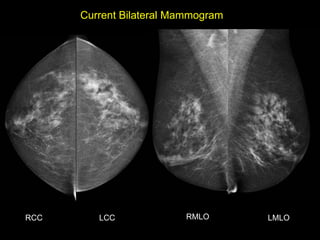

Dr. Vandana Dialani

HISTORY

• 65 yo female

• Presents from OSH with worsening ‘left

breast swelling’ for 8-9 months

• New 1 month history of ‘change in left

nipple’

Current Bilateral Mammogram

RCC      LCC             RMLO       LMLO

• What are the findings?

• What would you do next?